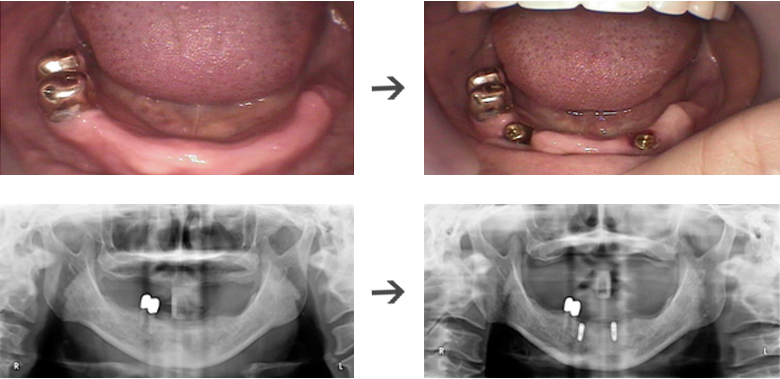

무치악 임플란트 시술전후